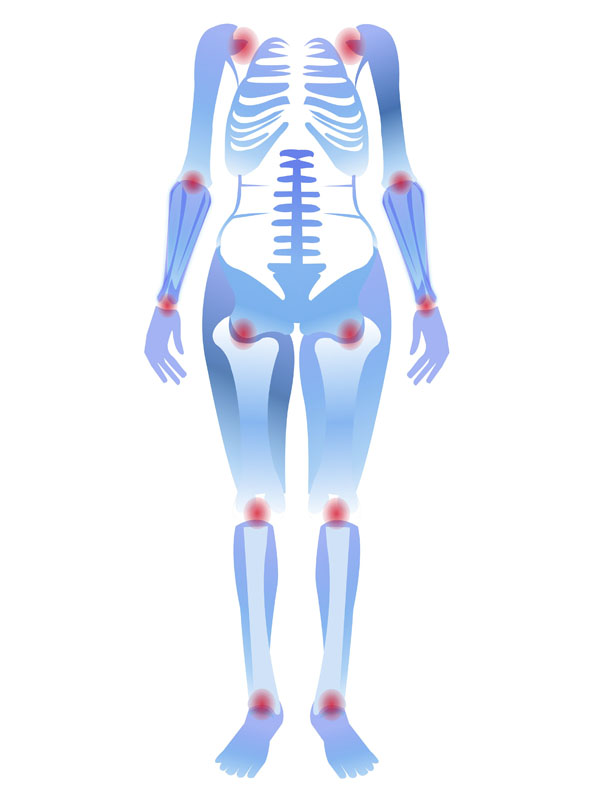

清晨下楼时膝盖“咔咔”作响,爬两层楼就酸胀发沉,久坐站起时关节像卡了锁……这些场景是不是很熟悉?保护膝盖的核心逻辑很简单:减少损耗+增强支撑。做好以下四件事,让膝盖多“用”10年。

避免”伤膝动作“,改掉坏习惯

选对运动,”养“出健康关节

注意保暖,及时”修护“

膝关节对寒冷刺激较为敏感,秋冬季节或长时间处于空调环境时,建议佩戴护膝做好保暖防护,减少寒冷诱发的关节不适。若关节出现持续性疼痛、肿胀,或伴随关节变形、活动受限等情况,切勿强忍拖延,需及时就医检查干预。早期通过规范治疗(如药物调理、专业康复训练等),能够有效延缓软骨磨损进程,保护关节功能。